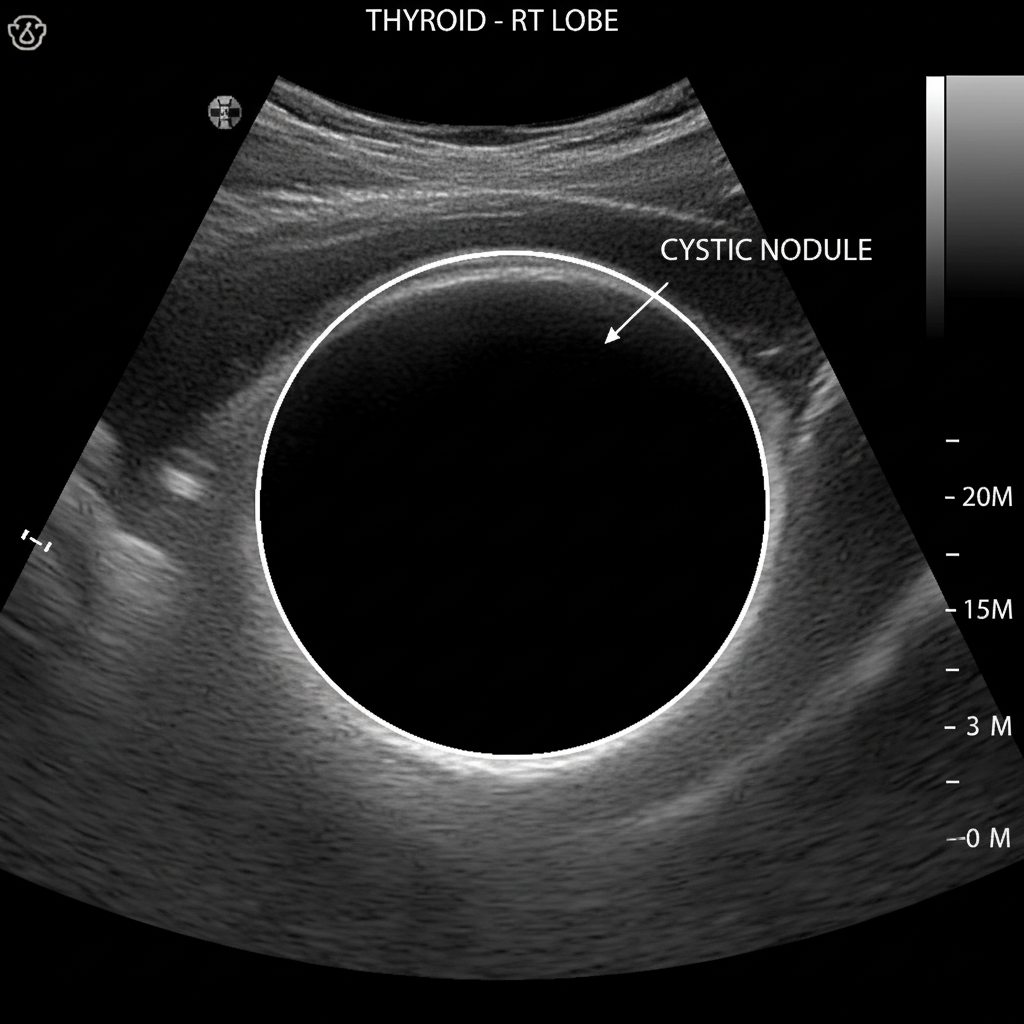

3. 목 앞부분의 멍울 또는 혹

세 번째는 목 앞부분에 만져지는 멍울이에요.

샤워를 하다가, 또는 거울을 보다가

목 앞쪽에 뭔가 볼록 튀어나온 것을 발견할 수 있죠.

이 멍울은 통증이 없는 경우가 많아서

그냥 지나치는 분들이 많더라고요.

하지만 이 멍울의 크기가 점점 커지거나

단단하게 느껴진다면 꼭 병원을 방문해야 해요.

초음파 검사로 간단하게 확인할 수 있으니,

절대 망설이지 마세요!

만약 초음파 검사에서

의심스러운 결절이 발견된다면,

미세침 흡인 세포 검사(조직 검사)를 진행하게 돼요.